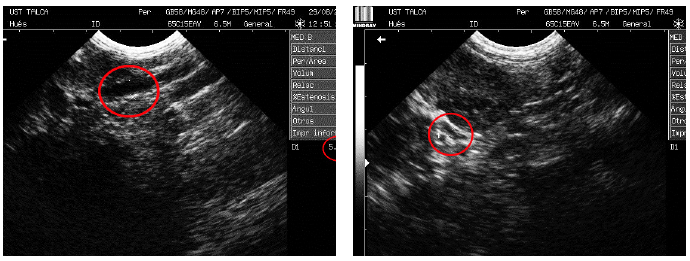

A la paciente se le realizó una ecografía abdominal (FIG. 1) (Ecógrafo digital MINDRAY Bio-Medical Electric Co., Ltd., modelo DP-6600 Vet, China), en la cual se observó un aumento en el grosor de la pared vesical (3 mm), sin sedimento. Ambas imágenes renales con límite córtico medular mal definido y relación córtico medular disminuida. Se observó además dilatación de la pelvis renal izquierda (1 cm de diámetro), así como también del uréter izquierdo (5,14 mm de diámetro, versus 2,74 mm de diámetro del uréter derecho) (FIG. 1a y FIG. 1b, respectivamente). Se siguió el recorrido de uréter izquierdo, dando la impresión de que no desembocaba en el trígono vesical, además se observó la presencia de una estructura tubular, anecoica, dirigiéndose hacia caudal, dorsal a la vejiga, y se descartó vasos sanguíneos, ya que se verificó la presencia de arteria aorta y vena cava, medial a esta estructura. Como conclusión a este examen se consideró uréter ectópico unilateral como el principal prediagnóstico, el cual debía ser confirmado mediante exámenes con contraste.